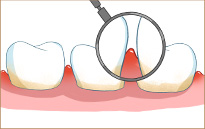

牙周病中(zhōng)期:出現牙周袋,有(yǒu)口臭、化膿現象

牙周病中(zhōng)晚期:牙槽骨吸收,患牙松動